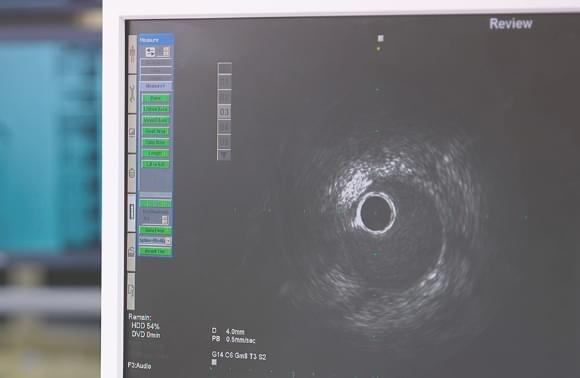

心筋梗塞や狭心症などの虚血性心疾患に用いられるカテーテル治療。このカテーテル治療の前の病態診断や治療後のステント留置の評価に使われるのが、「血管内イメージング(画像診断)」です。血管内イメージングには、血管壁、プラークの性質、病変長、対象血管径などを定量的に計測することが可能な血管内超音波検査法(Intravescular Ultrasound, IVUS)と高い解像度を有する光干渉断層診断法(Optical Frequency Domain Imaging, OFDI)の2つの方法があり、テルモはこの両方の技術を保有している数少ない企業です。高速演算処理により、リアルタイムに生じる心臓や肺の動きによる画像のずれを補正し、画像から血管形状やカテーテルの位置を検出させ、医療現場における診断を支援しています。